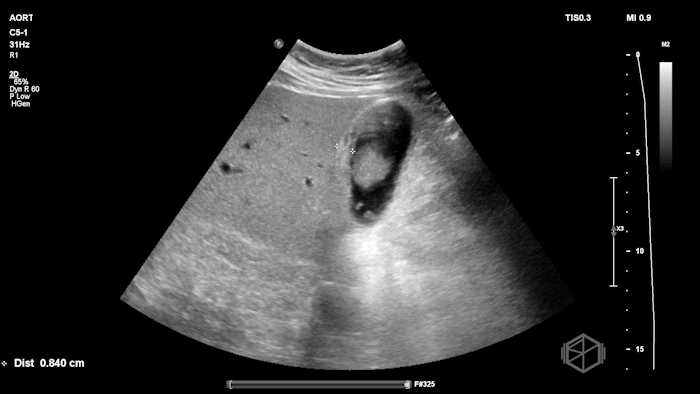

Their POCUS is below:

The POCUS demonstrated a thickened, edematous gallbladder wall with tumefactive sludge and gallstones, concerning for acute cholecystitis, though an underlying mass could not be excluded. A CT scan was obtained, which showed a layering gallstone versus gallbladder polyp, gallbladder wall edema, and possible pericholecystic fluid.

Surgery was consulted and recommended a radiology ultrasound, which predictably reported findings similar to the initial POCUS examination: gallbladder neoplasm versus tumefactive sludge versus non-calcified gallstones, with gallbladder wall edema concerning for acute cholecystitis. The radiology read recommended further evaluation with MRCP, which ultimately demonstrated findings consistent with acute cholecystitis without evidence of malignancy.

Diagnosis: Acute cholecystitis, tumefactive sludge